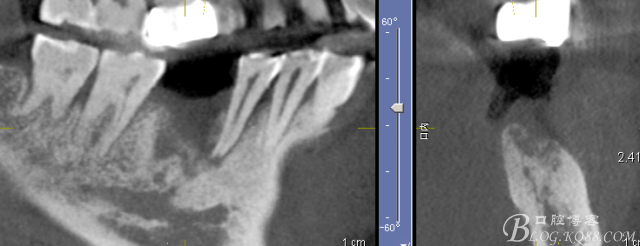

3月后復查見C5根尖有吸收

C6骨吸收明顯

患者希望功能上恢復,要求種植,不接受根管治療風險

三維檢查種植體位置,方向,平行度